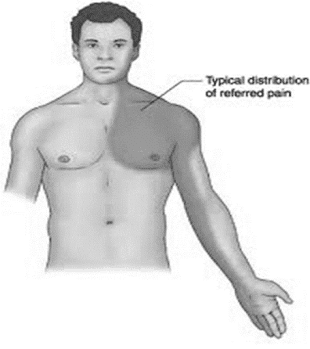

Symptoms of Angina Pectoris

• Gripping of central chest pain

• ↑ shortness of breath on exercise

• Sense of heaviness or numbness in the arm, shoulder, elbow or hand usually on the left side

• Constricting sensation in the throat

• Mild ache to severe pain

• Sweating and fear